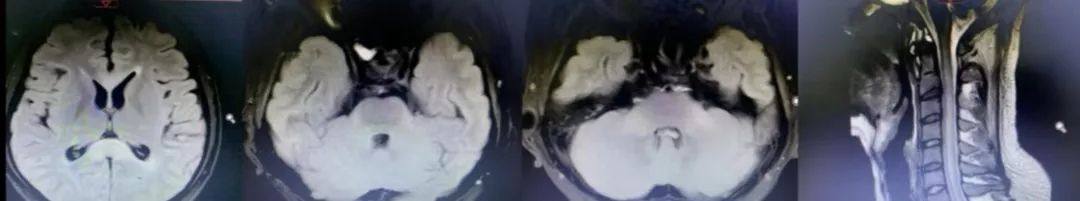

诊断脑栓塞是没有问题的,重点在于栓子来源的筛查。对于病因,群里老师们的总结已经很有一套;对于这个患者,却画风突变,1年后癫痫发作再次入院,颅脑影像如下:

答案:心脏黏液瘤。

近期群内发过一个手术切除后的心脏黏液瘤标本视频,直观生动印象深刻。心脏黏液瘤是最常见的原发性心脏肿瘤,占原发性心脏肿瘤的 50% 以上,70%发生在左心房。心脏黏液瘤具有良性特征,但因其质脆易碎易脱落进入血液循环并转移至全身其他部位,产生不良后果,心脏黏液瘤可具有以下3种心脏外转移的病理学过程:脑血管梗死引起缺血性卒中,实质性肿瘤定植、转移和肿瘤性多发性脑动脉瘤形成、伴或不伴出血。

1894年Marchand首次报道心脏黏液瘤导致多发性颅内动脉瘤形成,它是心脏黏液瘤的中枢神经系统并发症之一。心脏黏液瘤导致多发性颅内动脉瘤形成的可能机制有:(1)血管损伤理论:心脏黏液瘤细胞栓子脱落,经体循环进入脑血管,脑动脉末梢管腔直径小,瘤栓附着于微小动脉壁上,导致血管内皮损伤、瘢痕形成,引起颅内动脉瘤形成;(2)肿瘤定植理论:肿瘤细胞进入脑血管系统后,仍可以保持活力并在局部定植生长。肿瘤组织破坏血管壁,甚至血管壁整个基层均被肿瘤组织破坏、替代,这样可使得其在造影时不仅像真的动脉瘤一样呈瘤样扩张,还有造影剂明显滞留的表现。定植在脑血管内壁的肿瘤细胞有不同的生物学行为,不同的生长速度、方式,既可处于生长休眠状态也可最终坏死,这就可以解释迟发性病变以及多样的动脉瘤形态。在以上两种假说中,脑梗死事件都会发生。而多数学者赞同肿瘤定植理论,有文献报道在组织病理学研究中已经证明了动脉瘤壁中含有活性黏液瘤细胞的增殖及其对内弹力层的侵袭破坏。